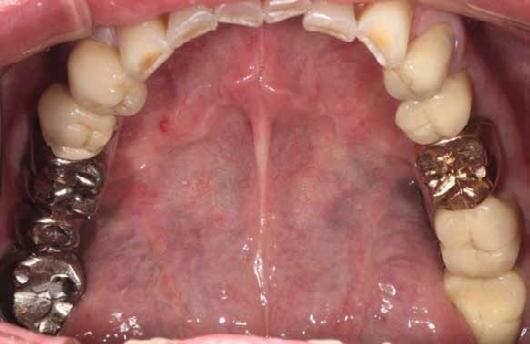

Fig 1. Patient anterior situation. Two anterior crowns fractured off.

Fig 2. Intraoral radiograph indicating tooth structural loss extent.

Fig 3. Provisional restorations on central incisors and gingival images. The gingival contours were optimal, and the gingival phenotype was thick.

Fig 4. Alveolar bone imaging. The alveolar bone was intact, and the alveolar crest was approximately 4mm apical to the restorative margin.